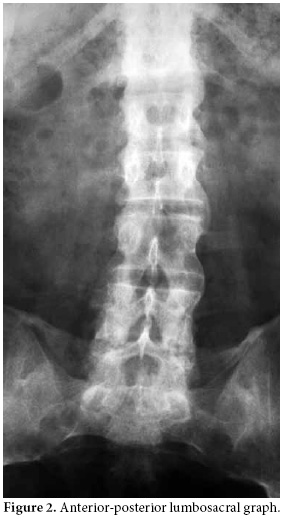

A 48-year-old male patient who had been followed up in another center with the diagnosis of AS was referred to our clinic with complaints of pain in the lower back, neck, and right hip increasing at rest and decreasing with activity. The locomotor system examination revealed that the cervical and lumbar vertebra motions were limited and painful. The motions of the right hip were painful, and extension and rotation were limited. The Mennel test and Patrick-Faber test were positive on the right side. The lumbar Schober test was 2 cm, and chest expansion was 2 cm. The anterior-posterior sacroiliac joint graph revealed bilateral stage IV sacroiliitis along with concentric narrowing in the joint space of the right hip (Figure 1), and the anterior-posterior lumbosacral graph revealed syndesmophytes (Figure 2). The patient was found to be human leukocyte antigen-B (HLA B27)(–). He had been followed up for seven years at another center with the diagnosis of renal failure associated with nephrolithiasis and had used sulfasalazine and leflunomide for AS. The patient had stopped using sulfasalazine and leflunomide on the recommendation of the nephrology department 1.5 months before attending our clinic. The patient was hospitalized for adjustment of his medical treatment. During follow-up, his temperature was 38-38.5 °C, and the patient developed abdominal pain. Detailed history revealed that the patient had been suffering recurrent attacks of fever and abdominal pain once a month for 15 years. At the time of the attack, the laboratory findings were as follows: Erythrocyte sedimentation rate (ESR): 74 mm/h, C-reactive protein (CRP): (++++), fibrinogen: 721.2 mg/dl (180-360 mg/dl), serum creatine: 1.6 mg/dl (0.5-1.2 mg/dl), blood urea nitrogen: 66 mg/dl (10-50 mg/dl), creatine clearance: 42 ml/min (71-151 ml/min), and microprotein in 24-hour urine: 333 mg/day (<150 mg/day). The patient had combined heterozygote M680I and M694V mutations of the MEFV gene which is common in FMF. There was no finding of hepatosplenomegaly on the abdominal ultrasonography. The gingival biopsy was negative for amiloidosis. The patient's daughter, who had similar attacks, was also diagnosed with FMF eight months after him. The patient was started on colchicine treatment (1.5 mg/day), and in the follow-up, he had attacks of abdominal pain and fever. His joint-related complaints regressed but did not completely resolve. The patient had been on leflunomid for 1.5 years and sulfasalazin for six months with no benefits and suffered from chronic renal failure. Thus, a TNF-α inhibitor (Adalimumab, 40 mg every other week) was added to the treatment regimen with colchicine after two months. After the patient used this combination for nearly one year, his complaints significantly improved. The patient had only one attack in that period. However, the patient's adherence to therapy was poor, and he did not use the TNF-α inhibitor for four months. He reapplied to our clinic with the complaint of increased joint pain. He reported one abdominal pain attack during these four months. The Bath Ankylosing Spondylitis Disease Activity Index (BASDAI) and laboratory findings of the patient before, during, and after dropping out of the treatment have been presented in Table 1. After the controls, the patient was restarted on TNF-α inhibitor (Adalimumab) treatment.

Familial Mediterranean fever is a disease usually seen among people with Mediterranean origin and is characterized with self-limited attacks of fever and polyserositis.[2] Articular involvement is the second most common presentation following abdominal pain.[13] One of the musculoskeletal involvement forms of FMF is spondyloarthropathy, and, almost always, HLA-B27 is negative. In these patients, generally minimal radiological spinal involvement is accompanied with unilateral or bilateral sacroiliitis, recurrent entesitis, and inflammatory low back and neck pain.[5] It has also been reported that AS may accompany FMF.[5,8,14] In our patient, a positive Schober's test, limited chest expansion, and the presence of bilateral stage IV sacroiliitis on the anterior-posterior sacroiliac joint graph with syndesmophytes on the anterior-posterior lumbosacral graph suggested FMF accompanied by AS.